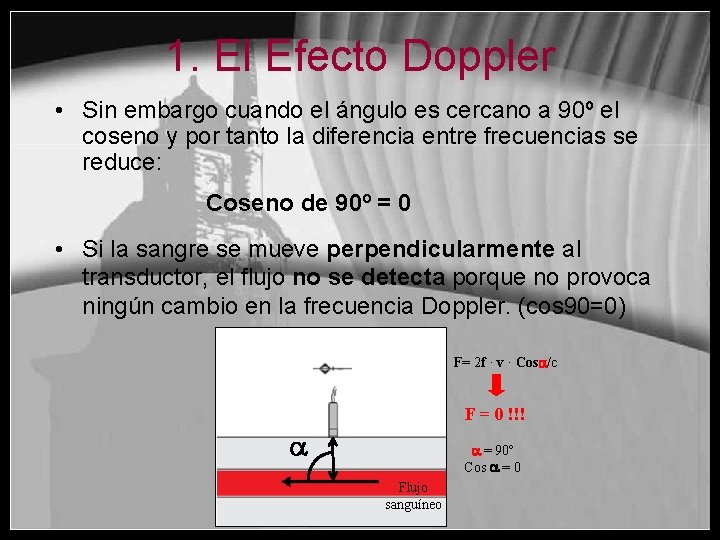

1. El Efecto Doppler • Sin embargo cuando el ángulo es cercano a 90º el coseno y por tanto la diferencia entre frecuencias se reduce: Coseno de 90º = 0 • Si la sangre se mueve perpendicularmente al transductor, el flujo no se detecta porque no provoca ningún cambio en la frecuencia Doppler. (cos 90=0) F= 2 f · v · Cos /c F = 0 !!! = 90º Cos = 0 Flujo sanguíneo